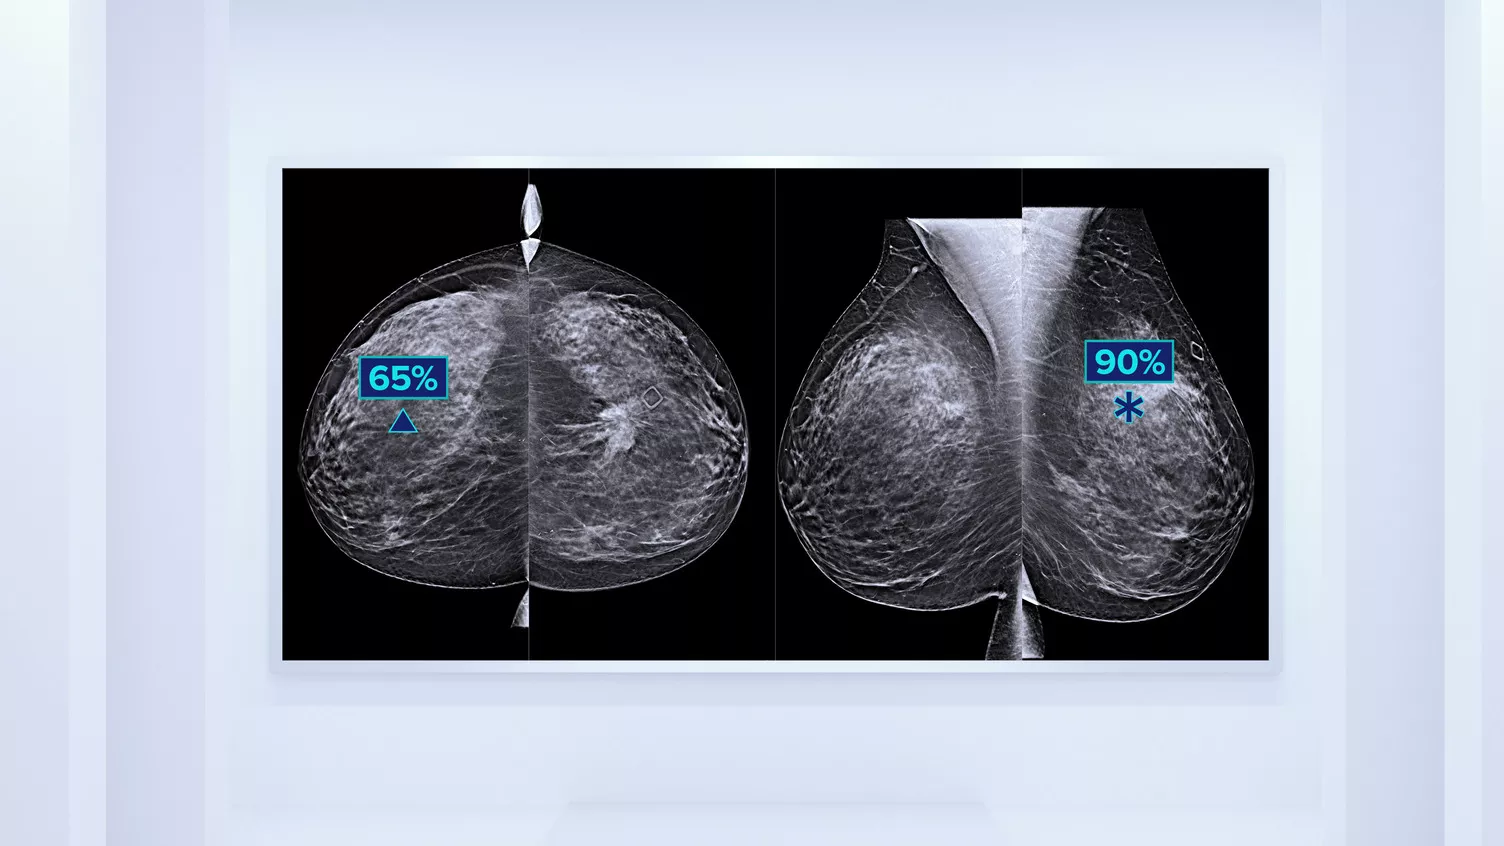

Eine höhere Brustdichte geht bekanntlich mit einem höheren Brustkrebsrisiko einher.1 Eine präzise, objektive Analyse ist daher entscheidend. Die durch maschinelles Lernen unterstützte Software der Quantra Technologie analysiert sowohl 2D™- als auch Tomosynthese-Bilder in Bezug auf Verteilung und Textur des Parenchymgewebes. Sie teilt die Brüste entsprechend der Leitlinie der 5. Auflage des BI-RADS Atlas des American College of Radiology (ACR) nach ihrer Zusammensetzung in vier Brustdichte-Kategorien ein.2

Neben dem Volumen können die Struktur und Textur des fibroglandulären Gewebes bei der Vorhersage des Brustkrebsrisikos eine ebenso wichtige Rolle spielen.3-5 Durch die Analyse und Einstufung der Brusttextur und -struktur der Patientin liefert unsere Technologie präzise Informationen, die Sie für eine konsistentere, zuverlässigere Bewertung und die zuverlässige Konzeption patientenspezifischer Vorsorgeuntersuchungen brauchen.

Objektiver Machine-Learning-Algorithmus, der die Brustdichte-Kategorie auf Basis der Analyse von Textur und Muster des Brustgewebes zuordnet.